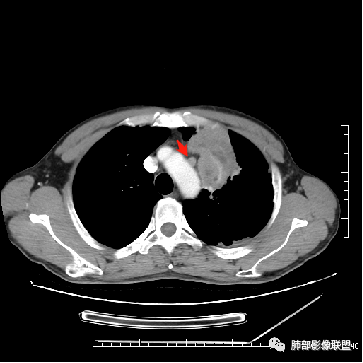

6.纵隔淋巴结肿大,密度均匀,强化均匀;

2.双上肺多发病灶,左肺上叶病灶沿血管支气管束分布,由外朝内,以平直收缩为主,周围有斑片渗出,胸膜糊墙,支持炎性病灶或是伴有肿瘤灶可能性。

两上肺发病,多支持结核等感染,但结核基础上伴发肺癌并不鲜见!

3.病灶内多支支气管粘液栓,炎性及恶性均可,但是炎性多于恶性;强化杂乱不均,病灶内小灶坏死比规则,支持炎性肉芽肿病变。

5.  本例的焦点主要集中在结核与周围型肺鳞癌的鉴别诊断上!

病灶与大气道的关系未能满意呈现,但如此大范围病灶紧贴胸膜却未见胸壁纵隔组织结构侵犯破坏是不大符合肺鳞癌的生物学行为的。